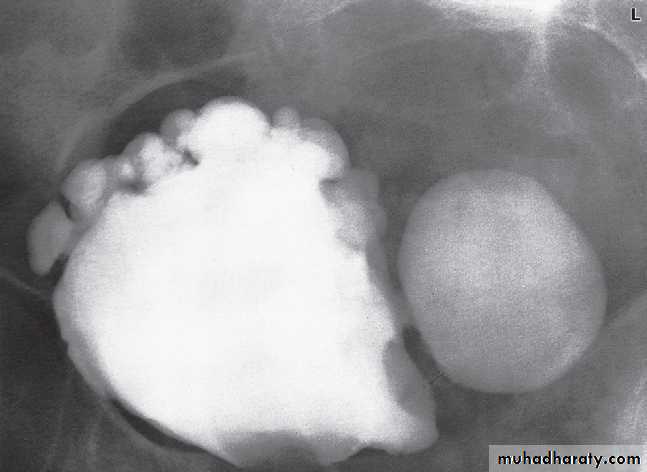

The bladder is the most frequent site for neoplasms in the urinary tract . Almost all are transitional cell carcinomas of varying degrees of malignancy.On ultrasound examination

bladder tumours are seen as soft tissue masses protruding into the fluid-filled bladder or as localized bladder wall thickening, . On rare occasions, there is visible calcification on the surface of the tumour, but the technique is poor for detecting extravesical spread.

IVU is less sensitive than ultrasound in detecting small bladde masses The main role of urography is todemonstrate any other lesions in the upper tracts (pelvicalicealsystems and ureters), as transitional cell carcinomasare often multifocal.